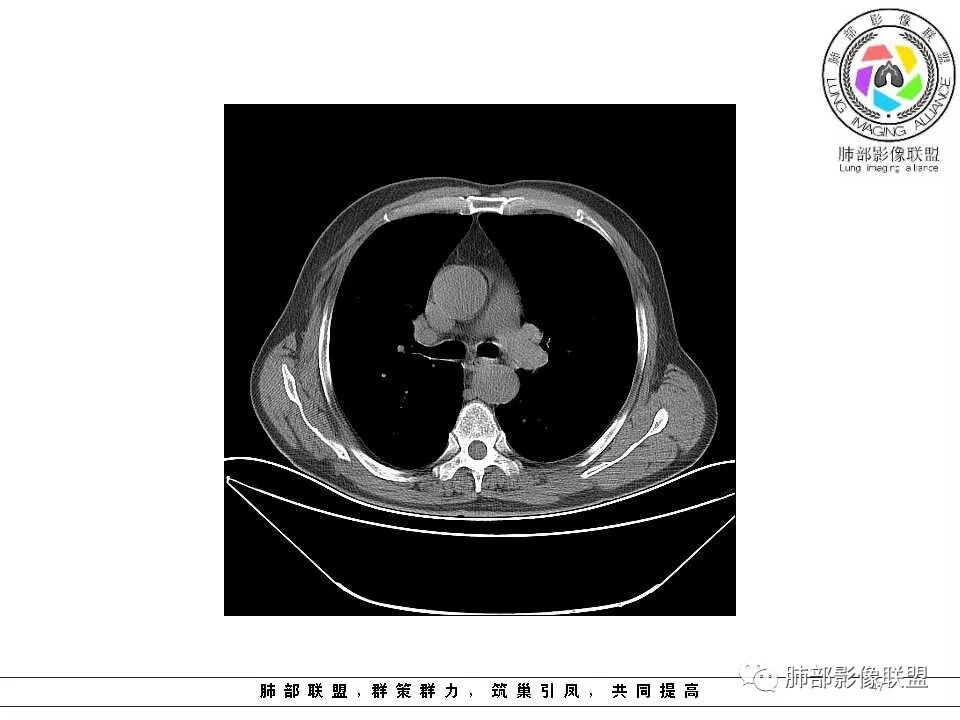

影像学特点:肺气肿背景下在大概一年的时间里出现了一个光滑的小结节,因为图像给的不是太薄,与支气管的关系判断不清,从结节周围出现斑片状炎症来判断,应该考虑结节位于支气管内,周围是阻塞性炎症,这样比较容易解释咯血

纵隔窗上似乎结节内可见点状高密度影,同时没有明显肿大淋巴结

所以我考虑支气管内的恶性肿瘤,类癌可能大。

左肺上叶光滑结节影 似乎与支气管没有关系  ,给的纵隔窗病灶中心似乎点状钙化  病灶旁有更小结节,与上一年片比较 结节增大明显  考虑恶性 类癌可能

老年男性,两肺可见小叶中央型肺气肿,提示应该有抽烟史。2016年片,右肺门支气管稍模糊,考虑慢性感染,纵膈淋巴结稍大。但2017年左肺上叶新发占位,堵塞支气管,引起局部肺不张伴感染,且纵膈淋巴结较2016年变大,患者同时伴有咯血,考虑恶性。鳞癌?类癌?小细胞?

肺气肿背景,2016年左肺上叶上舌段见微结节,2017年5月左肺结节增大,密度均匀,边缘光滑锐利,与邻近血管关系密切,血管贴壁走行,外侧见尖状突起,下舌段片状影,沿着支气管走行,内有粘液栓,考虑鳞癌,鉴别小细胞肺癌。

肺气肿背景,2016年左肺上叶上舌段见微结节,一年后左肺结节增大,密度均匀,边缘光滑、膨隆,似见小分叶,下舌段片状影,沿着支气管走行,内,老年患者,咯血1月。考虑恶性病变并阻塞性肺炎,鳞癌?注意鉴别结核。

前次片2016年4月20相应位置就有小点状病灶,2017-5-15呈结节影改变,边界膨隆,远端阻塞炎性改变,考虑肺癌,鉴别炎性结节!